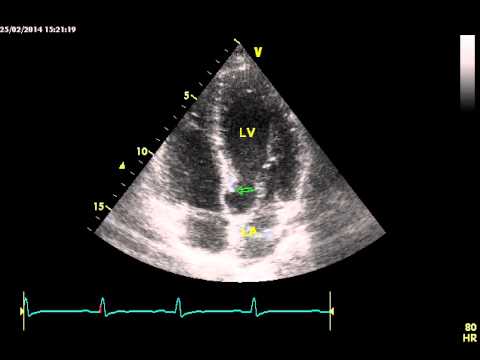

Мпп мжп

Мпп мжп 112 фото